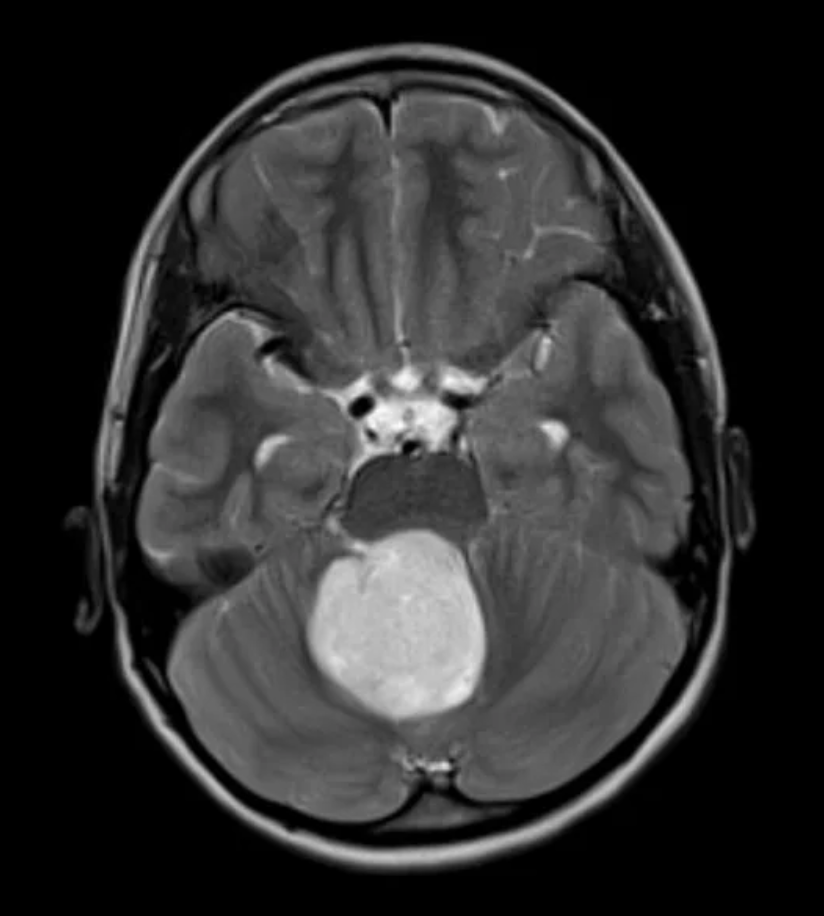

Symptoms vary depending on the tumor’s location and size and may include headaches, vomiting, seizures, weakness, balance problems, vision changes, back pain, scoliosis, or changes in bladder and bowel function. Early diagnosis, often through advanced MRI and CT imaging, is critical to optimizing outcomes.

Treatment is carefully tailored to each child and may involve surgery, chemotherapy, radiation therapy, or a combination of these approaches. Advances in neurosurgical technology—including neuronavigation, intraoperative imaging, neurophysiologic monitoring, laser interstitial thermal therapy (LITT), and minimally invasive techniques—allow surgeons to remove or treat tumors with exceptional precision while protecting vital brain and spinal cord structures.